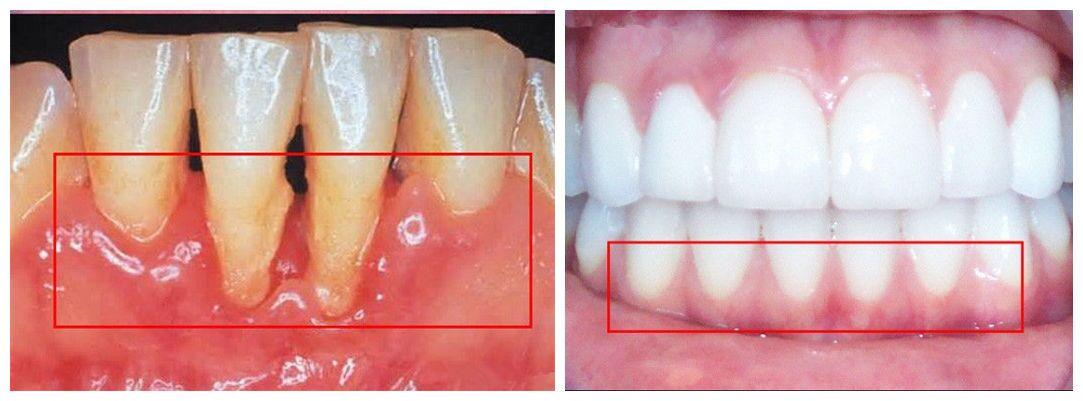

二、牙齿正畸之前如果发现牙槽骨吸收问题,需要针对此类病变先进性有效的控制。稳定之后如果牙槽骨状况符合可以正畸的条件,那么就可以对牙齿进行矫正。如果吸收问题比较严重,一般不建议做牙齿正畸。

三、如果牙槽骨的吸收比较严重,在治疗牙周疾病完成之后,可以根据患者意愿和经济能力进行牙槽骨修复手术,植入人造骨粉或者患者的自体骨,以此来恢复牙槽骨的功能。但此类手术的费用可能比较昂贵。